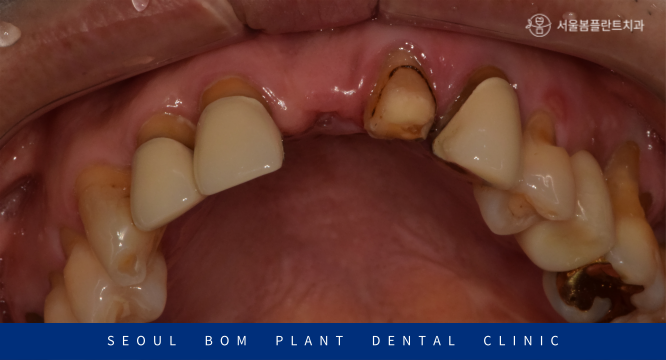

먼저 구강 내를  확인해 보았더니

위턱의 앞니가 오른쪽 두 번째 앞니(#12)부터

왼쪽 두 번째 앞니(#22)까지 총 4개의 보철물로 이루어진 브릿지 상태로

구강 위생 관리 부족으로 인해 잇몸 퇴축이 심하였으며,

외상으로 인한 충격으로 양측 첫 번째 앞니(#11,21) 사이가

파절되어 뒤틀려 있는 것으로 보였는데요.

이 경우 파절된 부위를 다시 접합을 시킨다거나

수정을 하는 것은 불가능하기 때문에

기존 보철물을 제거한 뒤 재보철치료가 필요하였습니다.